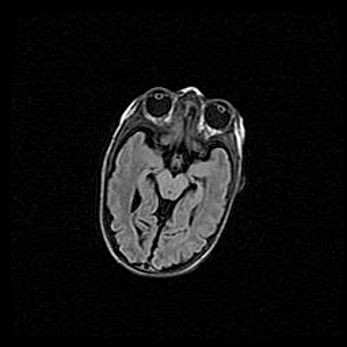

Сообщающаяся гидроцефалия. Кистозная энцефаломаляция головного мозга.

Возраст: 3 месяца 4 дня

Вес: 3100 г

Пол: женский

Окружность головы: 34 см

Срок гестации: 31 неделя

Кистозная энцефаломаляция головного мозга - одна из форм поражения головного мозга в детском возрасте. Характеризуется возникновением множественных и распространённых кист в коре, белом веществе и подкорковых образованиях головного мозга у плодов, новорождённых и детей раннего возраста. Развитие кистозной энцефаломаляции связано с внутриутробной асфиксией и гипотонией, родовой травмой, тромбозом синусов, пороками развития сосудов, инфекциями, сепсисом и другими причинами. Наиболее значимые инфекционные агенты: вирусы простого герпеса, цитомегалии, краснухи, токсоплазмы, энтеробактерии, золотистый стафилококк и другие.